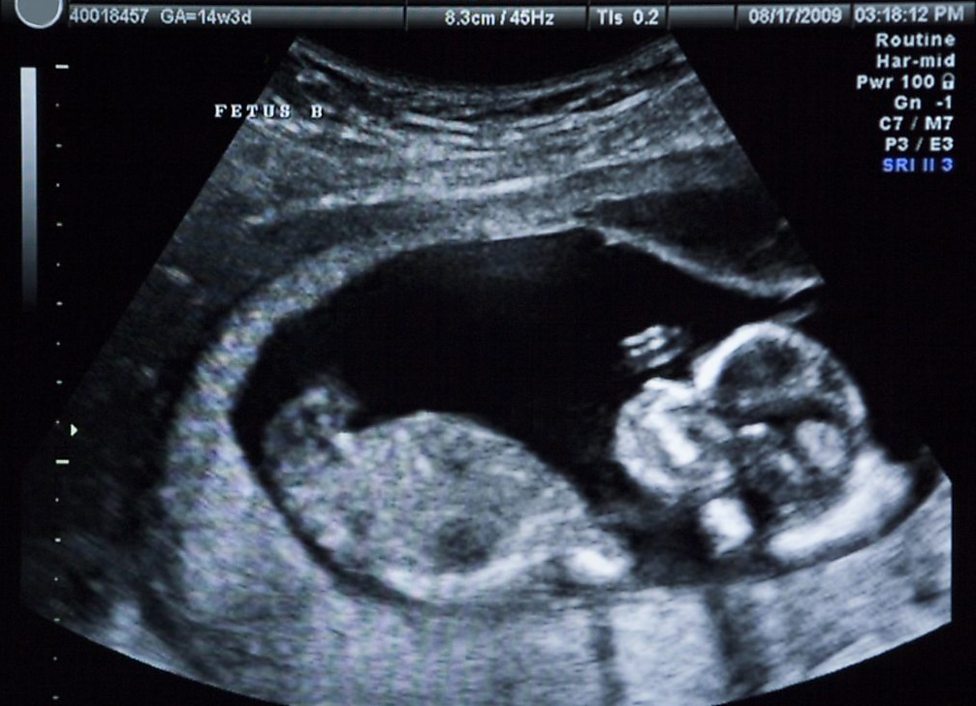

From lifecare.com.my

How Do Ultrasound Scans Work? LifeCare How Is Ultrasound Produced ultrasound waves are produced by a transducer, which can both emit ultrasound waves, as well as detect the ultrasound echoes reflected back. — how is ultrasound made? The source of the ultrasound wave is. — ultrasound testing, also known as ultrasonography or sonography, is an imaging test that uses sound waves to. ultrasound probes, called transducers,. How Is Ultrasound Produced.